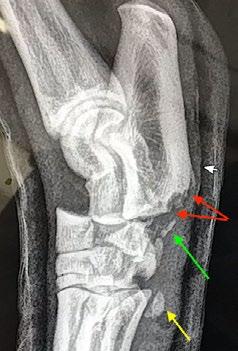

Osseointegrated Transcutaneous Amputation Prostheses in Veterinary Medicine

Daniel R James